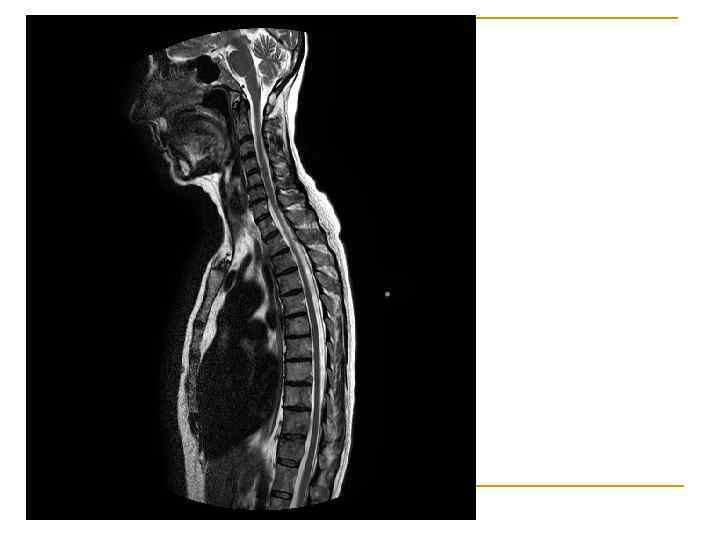

Вопрос 1. 6 Магнитно-резонансная нейротомография Физиология человека Под редакцией В. М. Покровского, Г. Ф. Коротько Медицина, 2003 (2007) г. Страница 97 -98.

Магнитно-резонансный томограф Signa MR/i фирмы «General Electric» 1 Тл

МРТ головного мозга